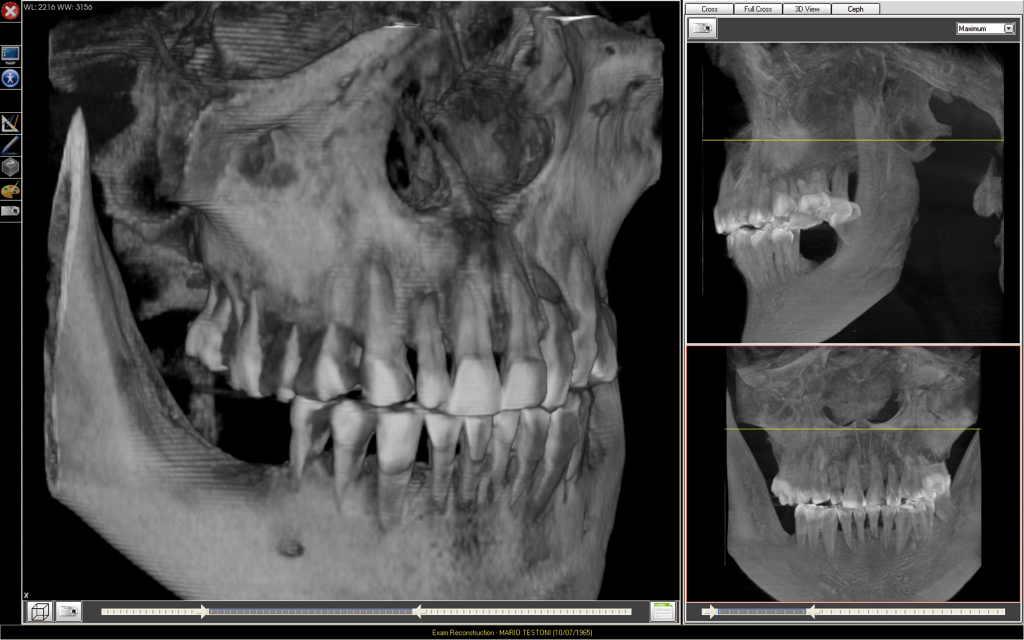

По снимкам дентального томографа терапевты смогут изучить направление нерва в каналах зуба, проверить количество каналов, найти застрявшие фрагменты инструментов, обследовать трещины, кисты и гранулемы на верхушке корня. У хирургов с 3D-снимками рабочей области будет четкая диагностическая картина для сложного удаления, в том числе ретинированных третьих моляров. Также без объемной картинки сложно предсказать результат работы с кистоподобными образованиями, травмами и опухолями зубочелюстной системы.

Снимок ортопантомографа очень информативен, но не показывает объем и качество костной ткани, не отражает реального состояния корней. К сожалению, за тенями корней зубов часто скрываются патологические изменения, а они в разы увеличивают риск послеоперационных осложнений. Ориентируясь только на двухмерный снимок, можно пропустить очаг инфекции в зоне имплантации, задеть нерв или крупный, аномально расположенный сосуд.

Имплантологу стоматологический томограф дает точные данные для позиционирования имплантата, включая ширину, высоту, плотность и качество костной структуры. Что, в свою очередь, позволяет выбрать правильный протокол и правильный имплантат.

В челюстно-лицевой хирургии только томограф позволит детально оценить локализацию, границы и распространенность патологического процесса челюстных костей или гайморовых пазух, определиться с объемом оперативных вмешательств и оценить результаты лечения.